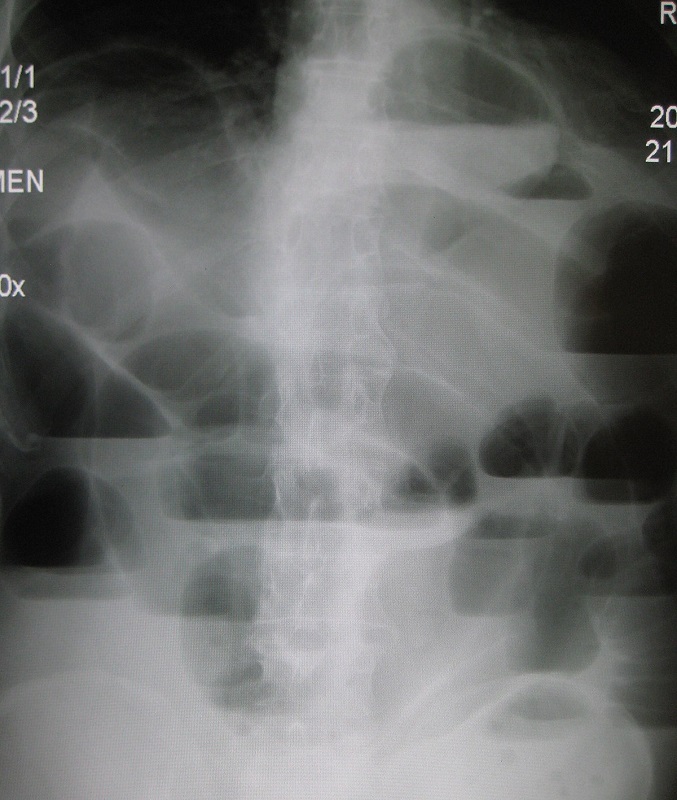

Trên các xét nghiệm chẩn đoán hình ảnh, bác sĩ có thể tìm thấy trên phim X-quang có các mức nước – hơi, hình chuỗi tràng hạt, CT scan thấy có hình ảnh chuyển tiếp giữa các đoạn ruột.

- Chụp Xquang bụng không tiêm thuốc cản quang/ có tiêm thuốc cản quang.

- Chụp CT ổ bụng.